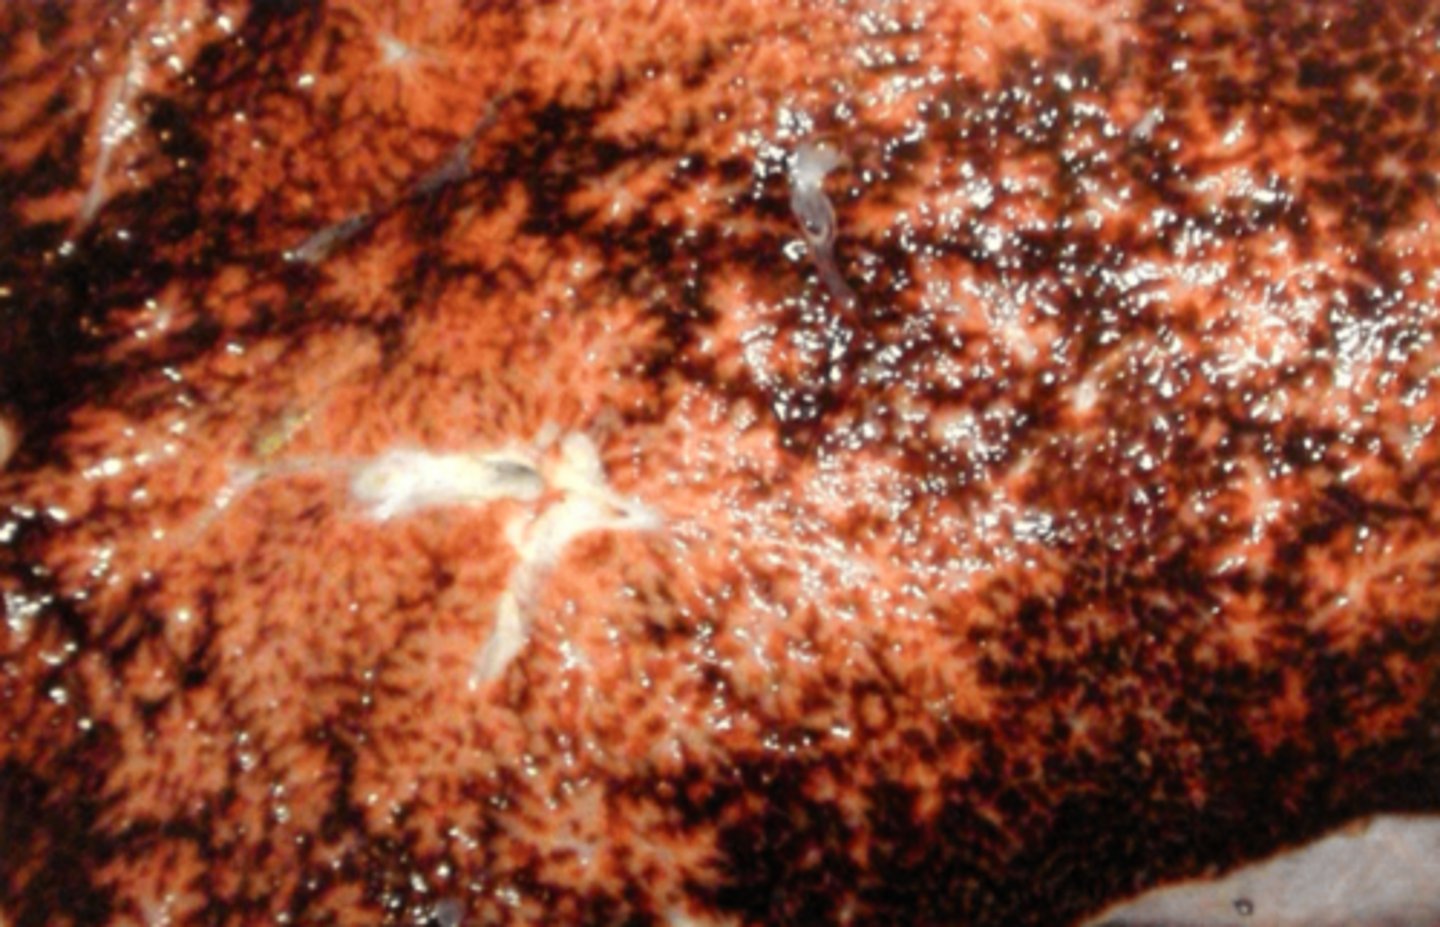

Akut, hæmorrhagisk og nekrotiserende hepatitis.

Ætiologi: infektion med Fasciola heptatica

Lever fra får, hvad er den patoanatomiske diagnose og ætiologien?